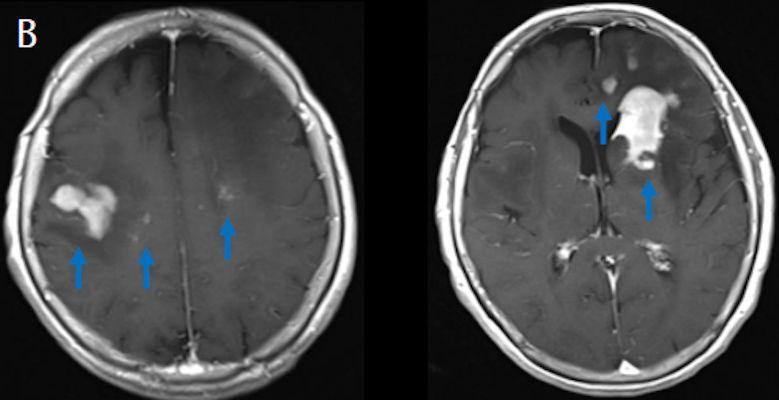

- (B) Aksiyel postkontrast T1A görüntülerde büyüğü sol frontalde kontrastlanma gösteren multipl kitle lezyonları (oklar) izlenmektedir.

- (C) Difüzyon ağırlıklı görüntülerde sol frontaldeki kitle lezyonunda difüzyon kısıtlama bulgusu (oklar) mevcut olup perfüzyon MRG’de rCBV haritasında belirgin perfüzyon artışı izlenmemektedir (ok).

- MRG’de, lenfomalar tipik olarak T2A sekanslarda hipointens olup DAG’de belirgin difüzyon kısıtlanması gösterirler.

- T2 sinyali belirgin düşük olgularda b=1000 görüntülerde hipointens görünüm izlenebilir ve T2 kararması (T2 black-out) etkisi olarak adlandırılan bu durum yanlış yorumlamalara yol açabilir. Bu nedenle gerçek difüzyon kısıtlamasını değerlendirmede ADC haritaları daha güvenilirdir.

- Perfüzyon MRG’de düşük-orta düzey CBV değerleri izlenir. Lenfomalarda düşük CBV değerleri, kötü prognoz göstergesidir.